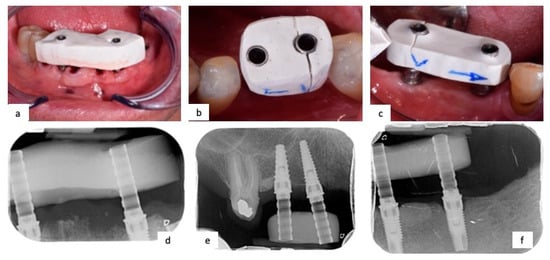

Below are reported three clinical cases: the first one the optical impression leads to a good outcome, without the fracture of gypsum check, unlike the last two cases that showed a bad outcome, fracturing the gypsum check (Figure 1).

Figure 1.

(a) Gypsum check screwed on abutments showed no fracture; (b,c) gypsum check fractured when screwed on abutments; (d–f) intraoral rx showed correct coupling between implant and abutments.